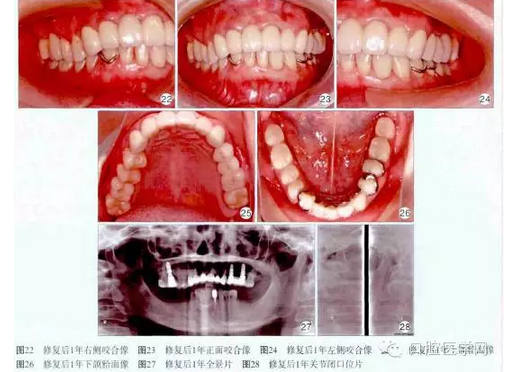

1個(gè)月后用Fuji玻璃離子水門汀(GC公司,曰本)永久粘固上頜烤瓷冠撟。修復(fù)后1年復(fù)查,患者訴義齒咀嚼、發(fā)音功能良好,舒適美觀,無壓痛。檢查:口腔衛(wèi)生良好,牙齦正常,種植體穩(wěn)固,咬合良好(圖22~26)。X線片示:16、24、26種植體頸部無明顯骨吸收,顳下頜關(guān)節(jié)維持原有狀態(tài)(圖27~28)。